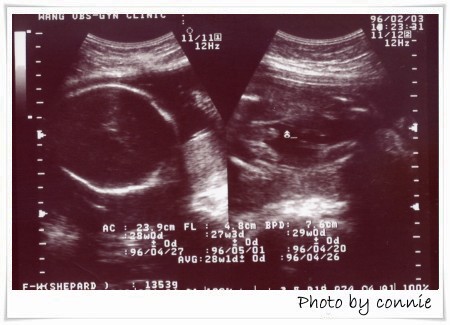

第五次產檢:

日期:96年01月06日

週數:23周+

血壓:139/90

尿蛋白,血糖:此次需抽血驗妊娠糖尿及B肝抗原,所以沒驗